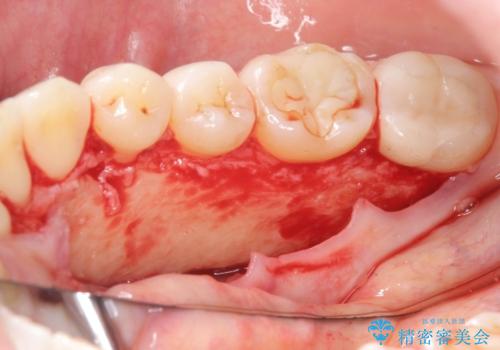

発音の邪魔となる骨隆起の除去

- 徐々に大きくなってきた骨隆起の除去を希望され来院されました。

下顎隆起を切除することで舌を収めるスペースを確保し発音のしやすさの向上を図ります。

手術は約1時間弱で終了し、術後もほとんど腫れは出ません。

- 外科手術のため、術後に出血、痛みや腫れ、違和感を伴います